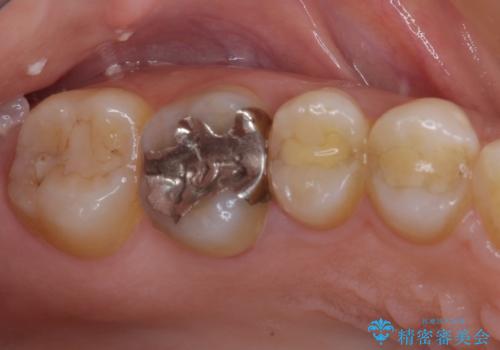

他にも銀歯や欠損となっている歯に対しての治療も希望されたため、補綴治療を行うこととしました。

インプラント治療をきっかけに、銀歯を全てセラミックに替えていきました。

人の目を気にせずに、大きく口を開けて笑えるようになりました。